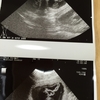

あどっちこないだからおしっこが赤い時があったので病院で採血と尿検査とエコー

結果は軽い膀胱炎でしょう〜って。

怖い病気じゃなくてあ〜よかった^^;

でも白血球がまだ少し高いので1週間後に再検査ですが・・・

とりあえずはそんなに心配しなくてよさそうです。

あどっち体重2週間前38.8キロ→今回39.5キロ

たくさん増えだしてうれしいな♪

先生もいい感じとおっしゃってくださった♪